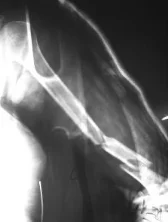

Humeral Shaft Fracture

- Possible associated injury to The Radial nerve (why?)(signs?)

Humeral Shaft Fracture- Management

- Conservative: U-shape slab) / splint / orthosis

- Gravity maintains reduction

- Management:

- Operative: (plate or IMN)

- Indications:

- Sever displaced Unreduced,

- Bilateral,

- multiple injuries

- floating elbow,

- Needs to use crutches

- Patients’ preference (active, athlete)